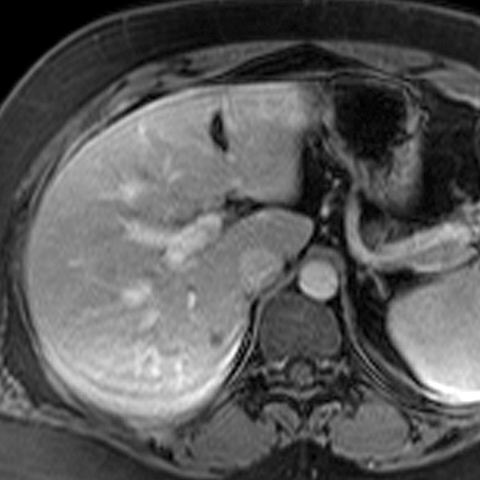

Normal Liver (T1- Weighted MR) [2 of 4]